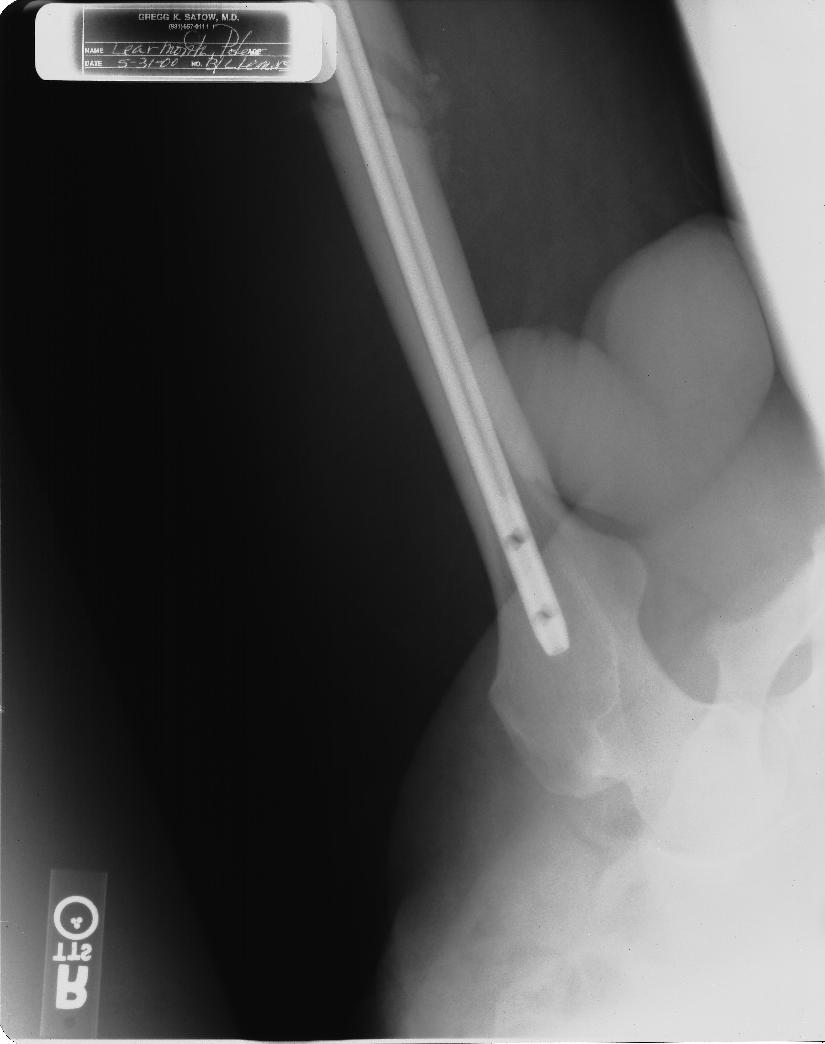

TitaniumLegs 8 #138 July 1, 2003 QuoteDude, you arent going with the shrinkage excuse are you??? OK, I confess. It's just like a penis only smaller! (©Chris DeBar) I'm not very good in bed, but at least it's over quickly. QuoteCome on show the side view.... Its all there in black and white. Show your penis!!! Noone else has had the balls. You asked for it... Edit: Now none of the girls are going to get any sleep tonight. (Come to think of it, neither will some of the boys!!) (>o|-< If you don't believe me, ask me. Quote Share this post Link to post Share on other sites